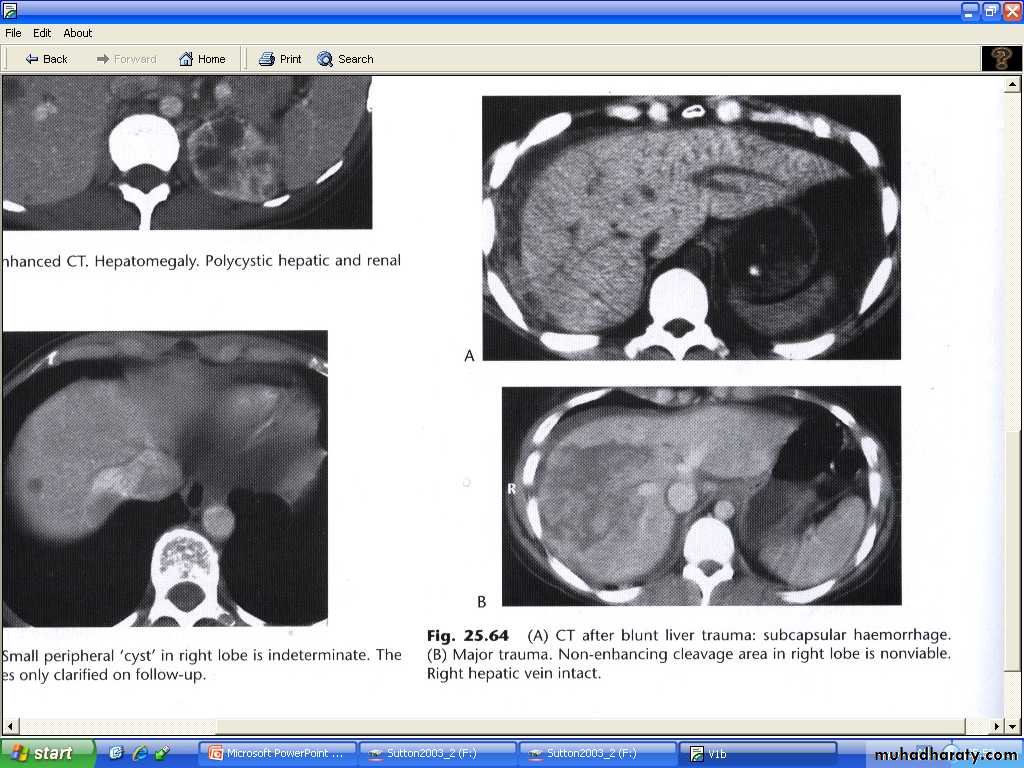

Liver trauma :

Is the commonest abdominal injury that leads to death.Features are : parenchymal lacerations , subcapsular and intrahepatic haematomas.

Lacerations and haematomas are recognized as low density areas relative to the contrast enhanced parenchyma , leakage of contrast indicate active bleeding .

Although US and MRI can demonstrate liver injury , CT is the best technique, which can survey other organs like spleen and kidneys. And identify any peritoneal fluid collection.